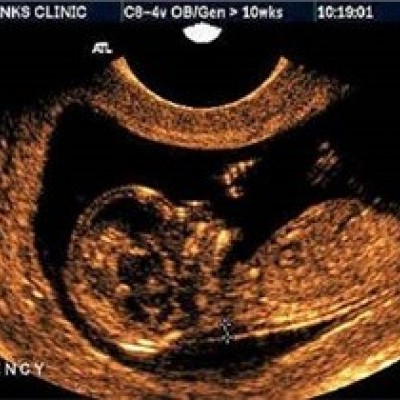

بارداری و زایمان

زمان بارداری

لزوم استراحت مطلق بعد از سونوگرافی در بارداری